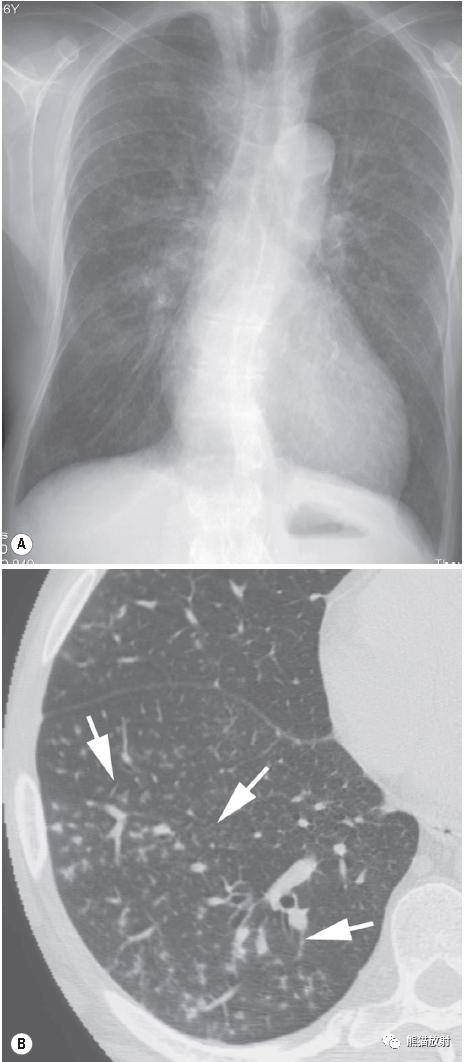

↑ 肺泡细支气管炎 Cellular bronchiolitis

71岁男性,持续发热48h。正位胸片正常,CT显示小叶中心分枝状结节和线状影,呈“树芽征” (a ‘tree-in-bud’ appearance) 。诊断为支原体性细支气管炎(Mycoplasma bronchiolitis)。